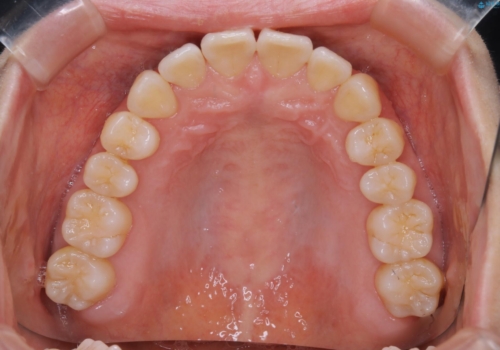

- 前歯のがたつきが気になるとご相談にいらした方です。右側前歯部のクロスバイトの他、左側にもシザーズバイトが認められたため、インビザラインにて治療を行いました。出産直後のため、ご自身の時間がなかなか取れないとの事で、最小限の来院回数で治療を勧められるように計画しました。

患者様ご自身で使用時間をしっかり管理して頂くことを条件に、最低限の来院回数で治療を進めていきました。20時間以上の使用を厳守して頂けたことで、少ない来院回数にて治療を終了することが出来ました。前よりも噛みやすくなったと大変喜んでいただけました。